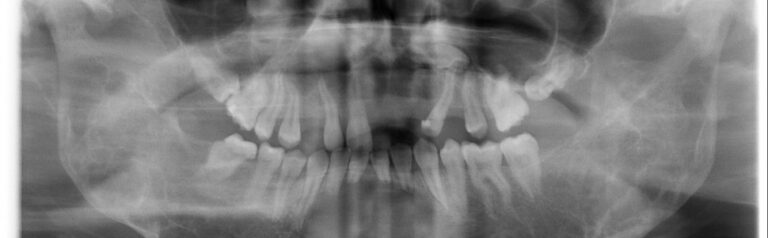

Czym jest elektrokoagulacja? Elektrokoagulacja to zabieg polegający na kontrolowanym wykorzystaniu prądu elektrycznego w celu zamknięcia naczyń krwionośnych oraz usunięcia zmienionych tkanek. W stomatologii metoda ta znajduje zastosowanie przede wszystkim w chirurgii i periodontologii. Stomatolog w nowoczesnej klinika stomatologiczna Kraków wykorzystuje…